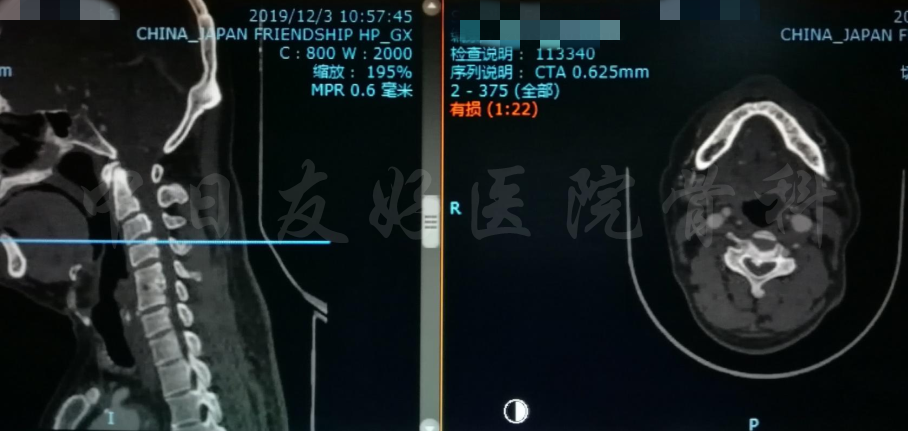

影像学检查

颈椎X片

颈椎MRI

颈椎MRI

颈椎各节段MRI(上下滑动)

颈CT(上下滑动)

腰椎MRI